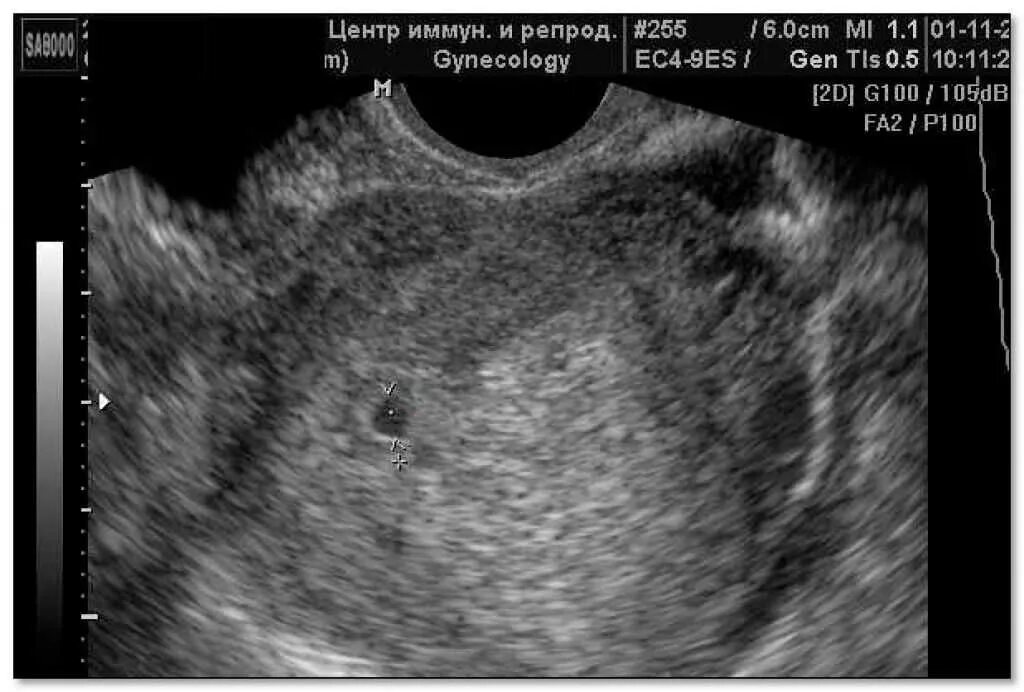

Как называется узи для определения срока беременности